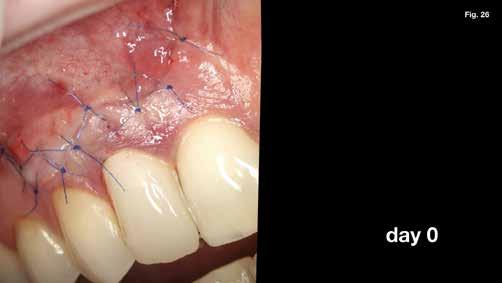

szárítottuk (18–20. ábra), majd retropecsétet (21–23. ábra) készítettünk „Neo Mta plus” (Avalon Biomed). A csontos blokkot visszahelyeztük (24. ábra) az eredeti helyzetébe, és a „Jason membrán” (Botiss Biomaterials GmbH) reszorbálható kollagénmembránt használtunk a blokkablak lefedésére (25. ábra). A lágyrészek varrására (26. ábra) nem felszívódó 6,0 monofilamentumos varratokat használtunk (SMI), amelyeket az 5. napon eltávolítottunk (27. ábra).

Eredmények: (3) és RAC-B összpontszám 2 (2-2-2/ 2) az 1 éves CBCT-követéskor (30–32. ábra), (4, 5,). Az 1 éves követéskor a lágyrészeken nem volt látható recesszió, csak enyhe színkülönbség a sebgyógyulás és a keratinizált szövet között, de ez a páciens számára nem aggályos (28. ábra).